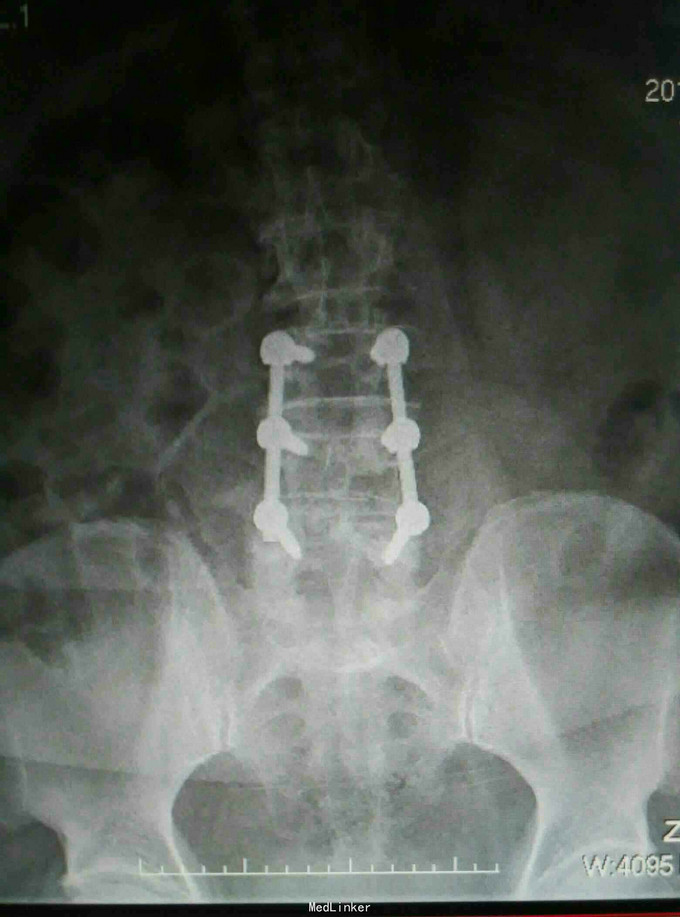

诊断:椎管内良性肿瘤,腰椎间盘突出 治疗:椎管内肿物切除+腰椎内固定

随访:术后加强腰背肌锻炼,定期复查。 讨论:患者症状要鉴别是肿物引起的还是椎间盘突出亦或是两者皆有,通过查体和片子更多考虑是肿物引起,术中做了肿物切除,进行内固定,患者术后症状好转也提示术前诊断是正确的。对于腰腿痛手术治疗前一定要明确诊断才能确保术后有较好的效果。